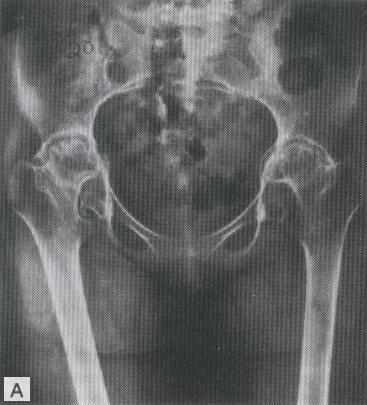

ENFERMEDAD DEGENERATIVA DE AMBAS CADERAS